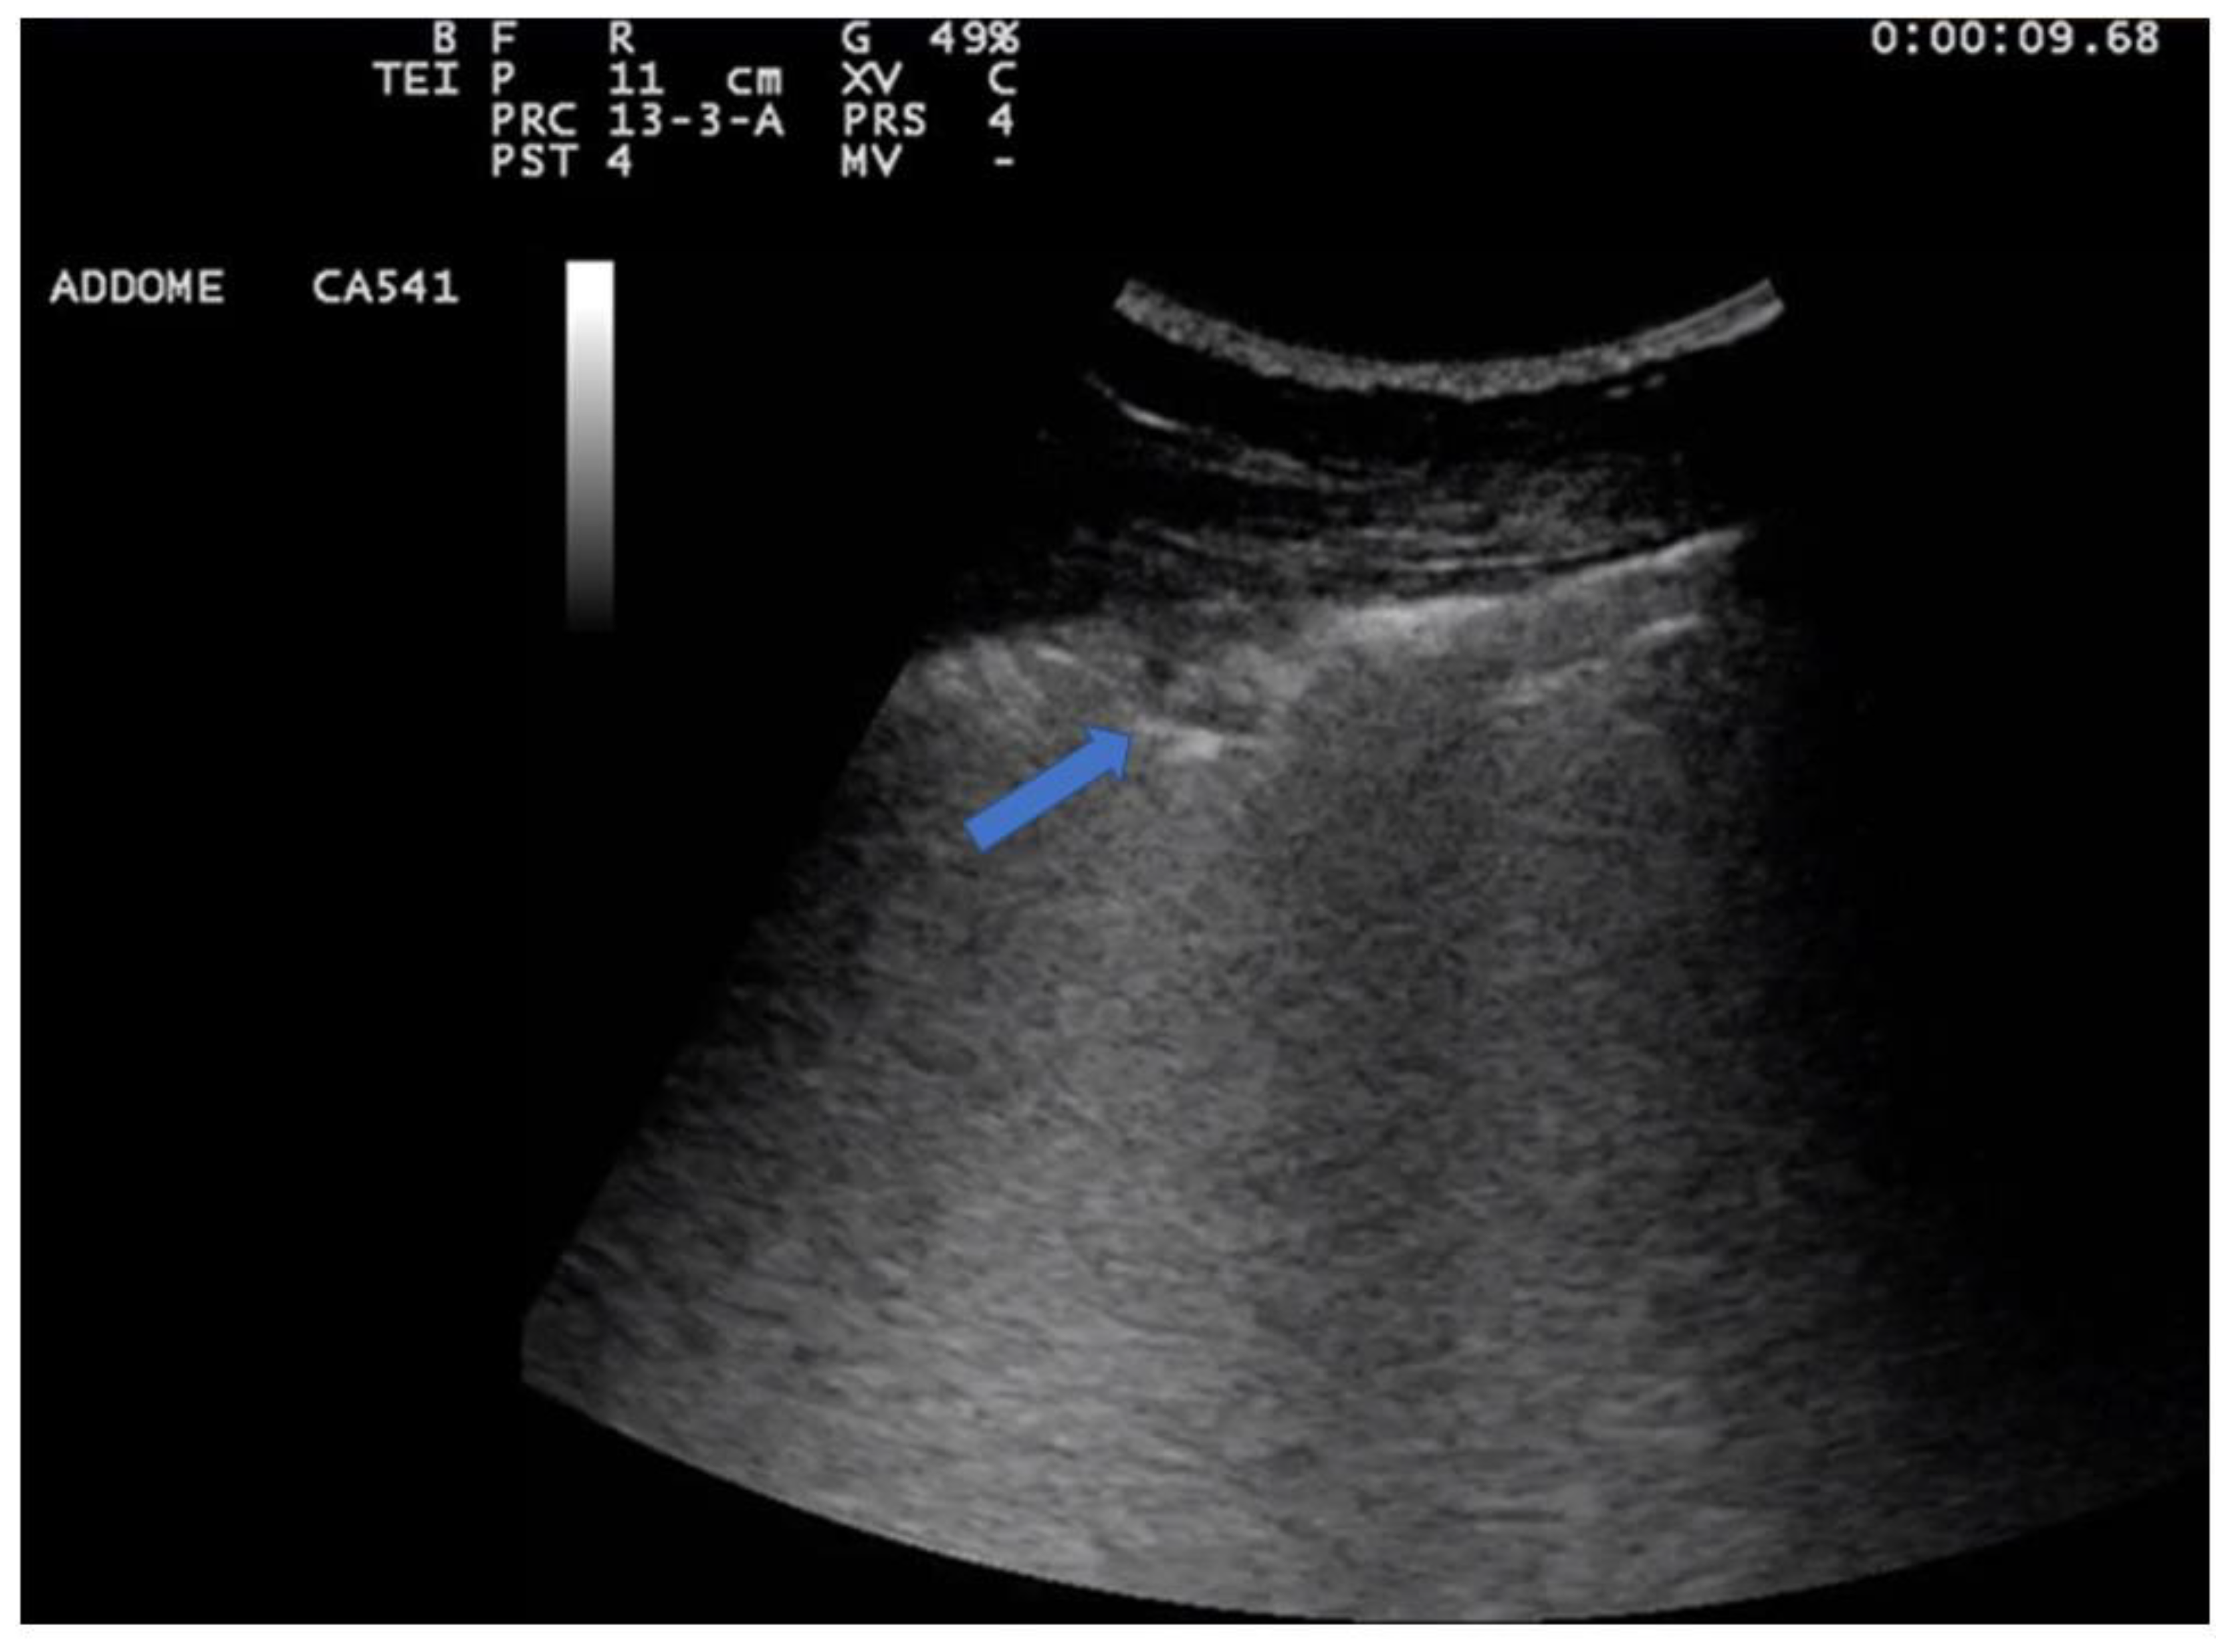

5.2. Lung Consolidations